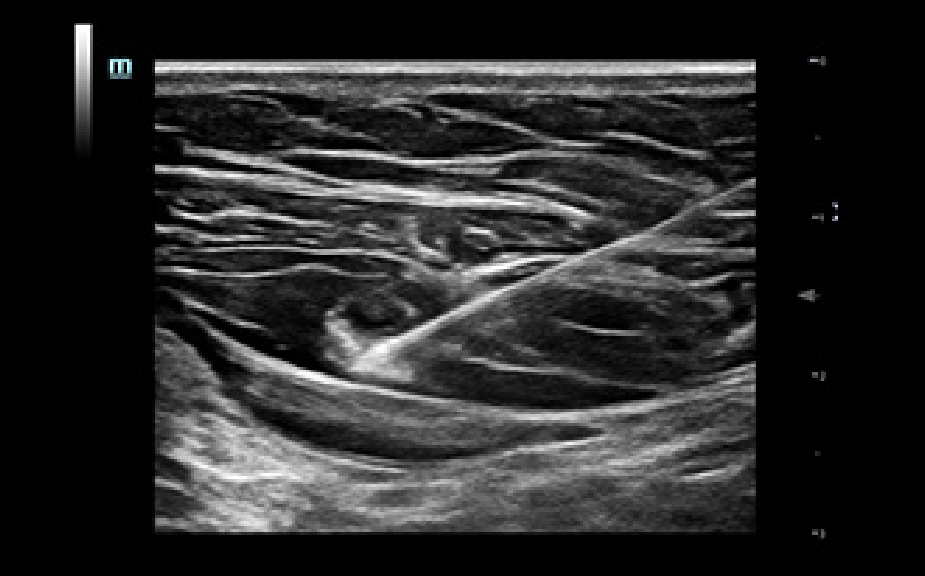

SoluciĂłn de punciĂłn para un solo operador